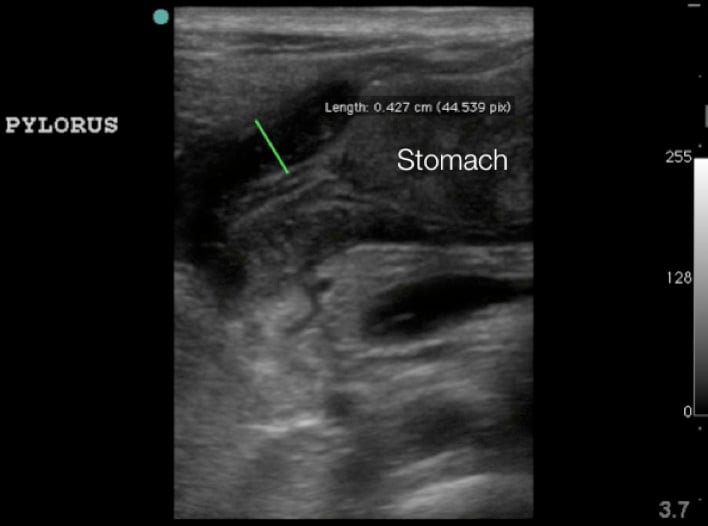

- Figure 2. Sonographic anatomy of the pylorus (P) in relation to the gallbladder (GB) and stomach (St)

- Figure 4a. Long axis view of the pyloric musle (M) highlighted by white arrows at the distal end of the stomach (St)